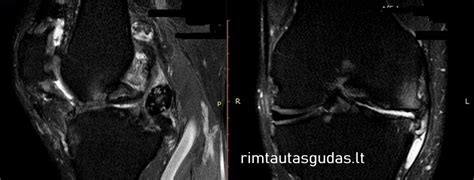

Magnetinio rezonanso tomografija (MRI) tapo auksiniu standartu diagnozuojant sinovines hemangiomas, ypač vaikų amžiaus grupėje. MRI naudoja stiprų magnetinį lauką ir radijo bangas, kad sukurtų detalius minkštųjų audinių vaizdus, be jonizuojančiosios spinduliuotės. Dėl šios priežasties ji yra saugesnė vaikams.

- Aukštas jautrumas ir specifiškumas: MRI yra itin jautri kraujagyslių anomalijoms ir gali tiksliai atskirti hemangiomą nuo kitų minkštųjų audinių darinių.

- Tiksli lokalizacija: MRI leidžia tiksliai nustatyti hemangiomos vietą sąnario viduje, jos dydį ir santykį su svarbiomis struktūromis, tokiomis kaip kremzlės, raiščiai ir meniskai.

- Ekstraartikuliarinių dalių vizualizacija: Viena iš svarbiausių MRI savybių yra gebėjimas vizualizuoti naviko dalis, esančias už sąnario ribų (ekstraartikuliariai) ar sunkiai pasiekiamose "aklose" vietose, kurias artroskopija gali praleisti. Tai ypač svarbu planuojant gydymą ir siekiant visiško naviko pašalinimo.

Rezultatai parodė, kad radiografijos neatskleidė jokių anomalijų, išskyrus minkštųjų audinių patinimą 8 atvejais. KT tyrimas taip pat nebuvo pakankamai informatyvus. Tačiau visais 7 MRI tyrimo atvejais buvo tiksliai nustatyta hemangiomos vieta, jos santykiai su intraartikulinėmis struktūromis, o 3 atvejais buvo pastebėta ir ekstraartikulinė naviko dalis.